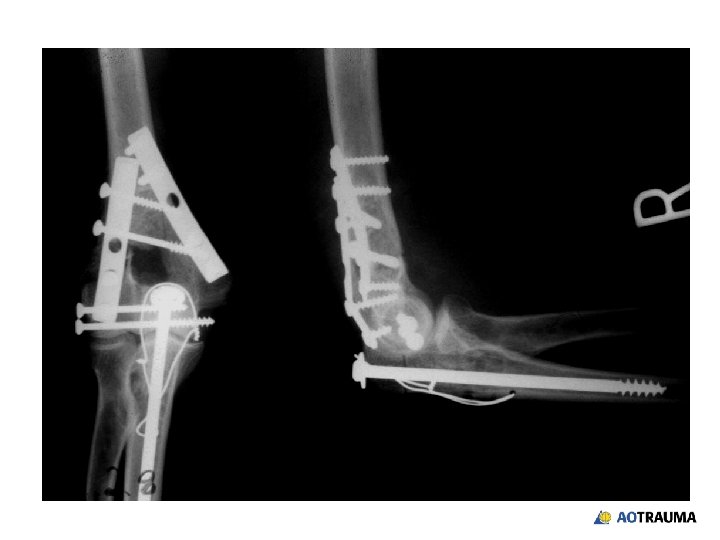

25 -year-old female, fall on the street • Dominant extremity • Closed isolated injury • Neurovascular status ok

What would your surgical approach be? 1. Posterior with olecranon osteotomy 2. Posterior—triceps reflection 3. 2 incisions—medial/lateral 4. Other

What would your choice of implant be? 1. Two conventional plates—parallel 2. One conventional plate—specialty type 3. Two conventional plates—orthogonal 4. Two locking plates—precontoured